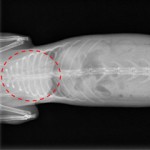

Q:12살 캬바리아를 기르고 있습니다. 7살 때부터 심장에 잡음이 들려서 정기적으로 병원에서 진료를 받고 있습니다만, 지난 번의 검진에서 장에 종양같은 것이 발견되었습니다.

종양검사를 위해서는 마취를 해야 할 필요가 있습니다만, 심장이 좋지 않기 때문에 마취를 해서 검사를 받고 싶지 않습니다.